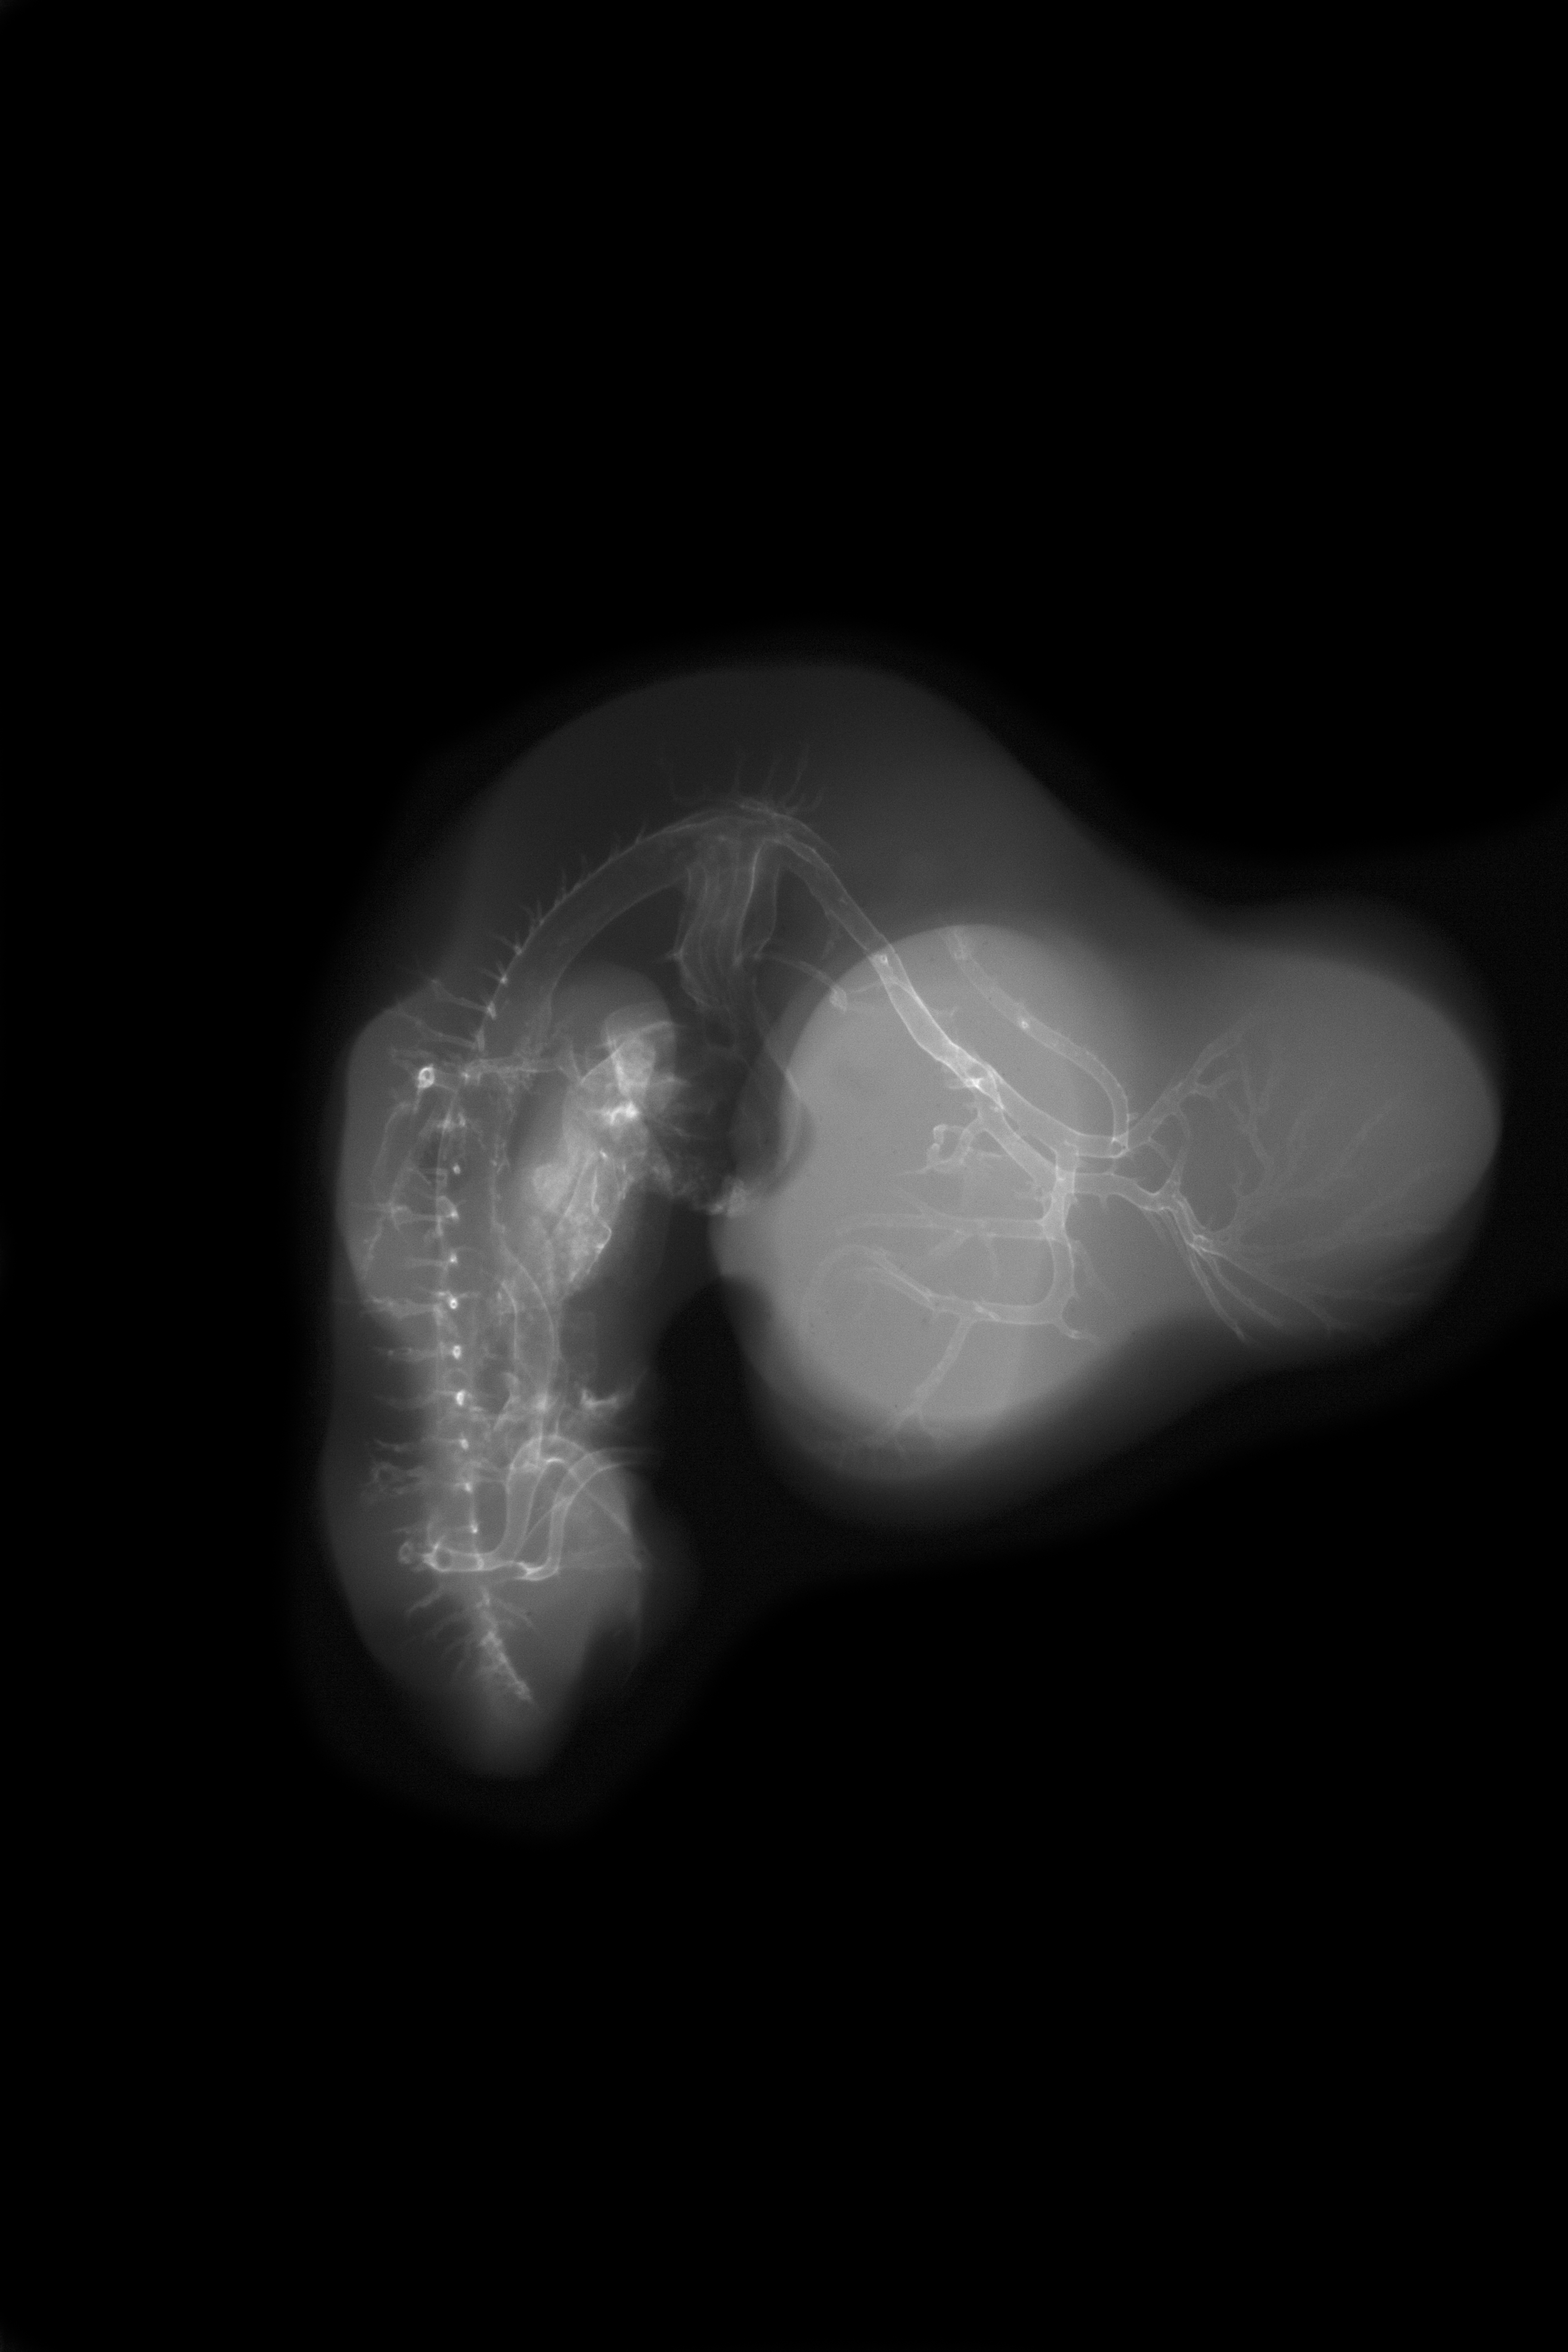

Chick Embryo Microangiography

Hamburger-Hamilton (HH) Stage 27 (approx. 5 - 5.5 days)

Stereo X-Ray Micrographs